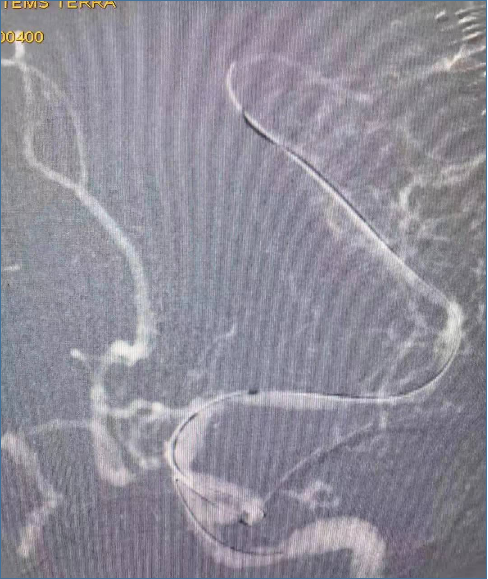

术中造影(LCA):可见左侧大脑中动脉 M1段近端和远端两处狭窄

Synchro-14 微导丝(0.014in×300cm)超选至左侧大脑中动脉M2段远端,同轴输送Gateway球囊(1.5mm×15mm)至左侧大脑中动脉M1段远端狭窄段行球囊扩张治疗(6atm)。

球囊扩张后5分钟,造影显示左侧大脑中动脉M1段远端狭窄无回缩、穿支血管无闭塞、远端血管血流通畅。

Synchro-14 微导丝(0.014in×300cm)超选至左侧大脑中动脉M2段,同轴输送Gateway球囊(2.0mm×9mm)至左侧大脑中动脉M1段近端狭窄段行球囊扩张治疗(6 atm)。

M1段多发狭窄球囊扩张后5分钟,造影显示左侧大脑中动脉、分支血管以及远端血管血流通畅,穿支血管无闭塞,M1段多发狭窄无回缩。